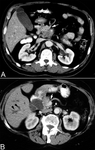

Contrast enhanced abdominal computed tomography scan showing (A) a large mass in the head of pancreas with encasement of the superior mesenteric artery (white arrow) and (B) dilated intrahepatic ducts (black arrowheads) and encasement of the superior mesenteric vein (white arrow)

Takhar AS et al. BMJ. 2004;329:668